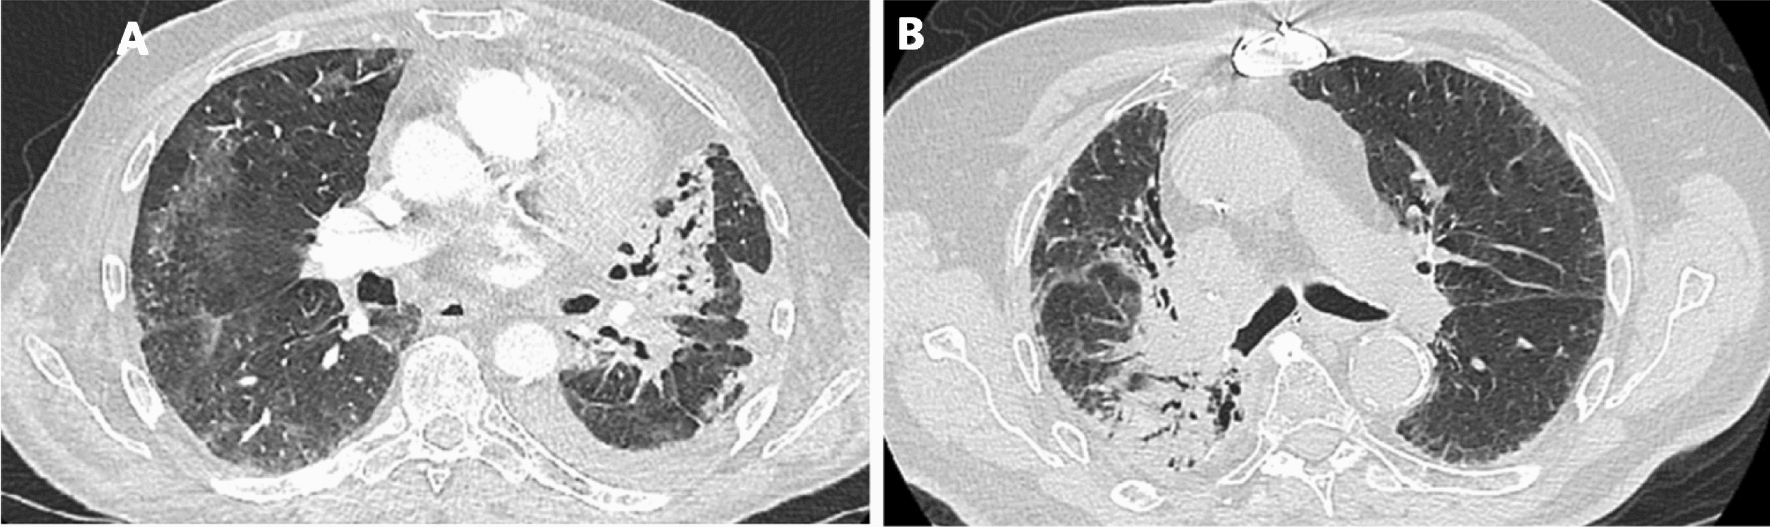

Radiotherapy is used consistently throughout lung cancer treatment. Radiation pneumonitis (RP) is a common complication of thoracic radiotherapy. According to the relevant literature, the incidence rate of RP is approximately 30% [1]. RP occurs when normal lung tissue in the radiation field is affected by passing radiation, which causes alveolar exudation inflammation. It is typically marked by dyspnoea, dry cough, hypoxemia, and low fever. Pathological anatomy shows alveolar septal oedema, endothelial cell swelling, vascular wall thickening, and other changes [2, 3]. The main manifestations of CT are patchy and uniform flocculent blurred shadows in the radiological field, accompanied by thickened blood vessels and bronchial shadows and indistinct boundaries with surrounding normal lung tissue. The spots in the radiological area are solid, with a higher density than ground glass opacities, clear edges, and clear boundaries with normal tissue [4]. We attach CT images to demonstrate the above features (Fig. 1).

Fig.1.

CT image of RP A: Axial image from a CT angiogram performed 5 months after radiotherapy demonstrating consolidation and atelectasis consistent with radiation pneumonitis and fibrosis. B: The image demonstrates airspace consolidation in the medial right middle lobe and superior right lower lobe with traction bronchiectasis and reticulation within the radiation field, consistent with evolution of radiation fibrosis